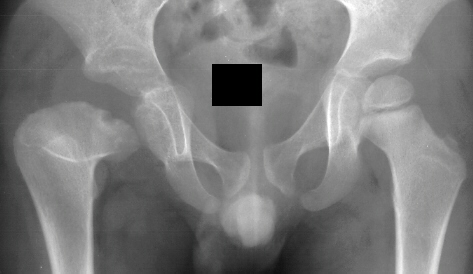

- 2 month Office Follow Up: Rt hip Xray: progressive destruction of capital

femoral epiphysis, cystic changes in metaphysis consistent with AVN.

- Age 6: Valgus osteotomy for subluxation and 2cm leg length inequality.

- Age 15: Valgus osteotomy for hip incongruity.

- Age 20: Hip arthroscopy. Hip fusion recommended.

This case is an example of untreated septic arthritis which caused avascular

necrosis of the proximal femur. The primary cause of this is undrained

septic hip. Repeated aspiration is not adequect treatment of a septic hip.